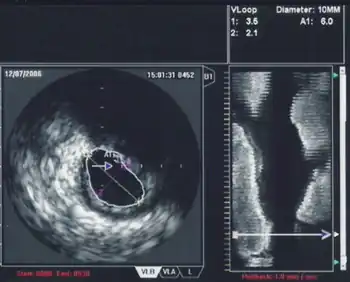

Transthoracic echocardiography (TTE)

Transthoracic echocardiography (TTE) uses ultrasonic waves for continuous heart chamber and blood movement visualization. It is the most commonly used imaging tool for diagnosing heart problems, as it allows non-invasive visualization of the heart and the blood flow through the heart, using a technique known as Doppler.

TTE is commonly used to evaluate patients with coronary artery disease.[4] Stress echocardiography is used to diagnose coronary artery disease and assess myocardial viability.[4]